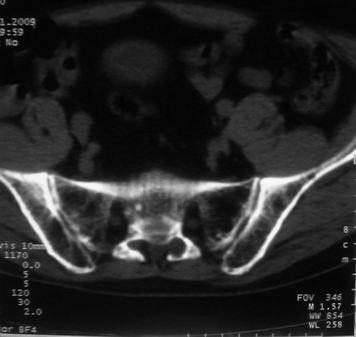

男,85岁,排尿困难。骶椎有问题吗?

1)考虑前列腺增生症并阻塞性膀胱炎。2)骶椎右侧类似囊状骨质密度减低区,边缘骨质硬化,其内为软组织密度影填塞,相邻之骶椎椎管受压变形;考虑为骶椎右侧囊肿或神经纤维瘤。

建议:行mri检查。

骶椎脊索瘤

1)前列腺明显增大,突入膀胱,各叶比例协调,密度均匀,精囊腺及精囊角正常;考虑前列腺增生症并阻塞性膀胱炎。2)骶椎右侧类似囊状骨质密度减低区,边缘骨质硬化,其内为软组织密度影填塞,相邻之骶椎椎管受压变形;考虑为骶椎右侧囊肿或神经纤维瘤。